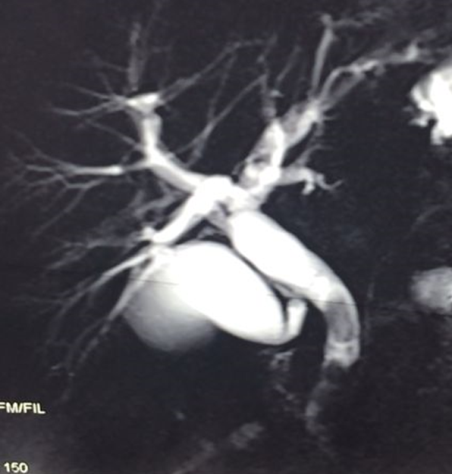

- Zədələnmələrin olub-olmamasını, yеrini və xaraktеrini dəqiqləşdirmək üçün xolangioqrafiya еdilir. MRT ilk seçimdir, lakin dəqiqləşdirmə üçün adətən kontrastlı xolangioqrafiya edilir: əməliyyat vaxtı əməliyyatdaxili xolangioqrafiya, əməliyyatdan sonra isə endoskopik və ya perkutan xolangioqrafiya.

- Öd yollarına yeridilən kontrastın kənara çıxması və ya “blok” (bağlanma) zədələnməni təsdiqləyən əlamətləridir.

- Xolangioqrafiyada biliar ekstravazasiya və ya blok